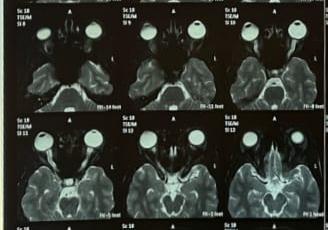

CASE 1

A 27 y old female appeared with a month's worth of headaches and hazy eyesight. Severe Headache was evident on both sides of the occipital region, along with nausea. For one month, the patient had blurred vision that lasted only a few seconds and resolved spontaneously. Her BMI was normal when she was examined. There was no major personal or family history. The intraocular pressure in both eyes was 17 mmHg, according to aplan tonometry. Light perception and projection were present in both eyes. Both eyes showed a papillary light reflex. Ophalmoscopy of both eyes revealed papilledema, no boundaries on the optic nerve head, dilated retinal veins, and a chrysanthemum flower in the right eye. Visual field tests found an increasing blind spot in both eyes, as well as some paracentral scotoma. The lumbar puncture was conducted with a high opening pressure of 250 mmH2O. The CSF test revealed no abnormalities. All required blood tests were performed, which turned out to be normal. The MRI brain with orbit revealed flattening of the posterior sclera, protrusion of the optic nerve heads, and vertical tortuosity of the optic nerve sheath, which suggested the likelihood of pseudotumour cerebri fig. 1. Because of the minor visual field loss, treatment began while in the hospital with mannitol (20%) TID and acetazolamide 500 mg BD. Methylprednisolone injections (1g/d) were given for 5 d. Before being discharged from the hospital, it was recommended to limit physical activity and treat with acetazolamide 250 mg BD and oral prednisolone in decreasing doses. After a month, the follow-up assessment indicated maximal visual acuity in both eyes without correction. An opthalmoscopy examination indicated bilateral mild papilloedema. The study of the visual field indicated very minimal modifications. After a two-month follow-up, there was no Papilloedema and no headaches or blurred vision.

Fig. 1: MRI brain with flattening of posterior sclera and protrusion of optic nerve head